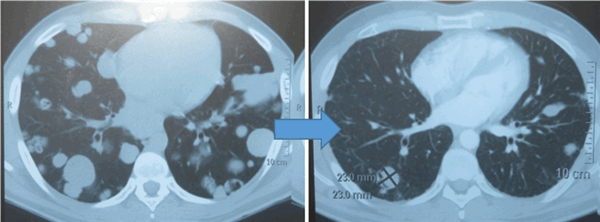

Показания к химиотерапии определяются степенью распространенности процесса, наличием легочных/внелегочных метастазов. Стандартным режимом химиотерапии при герминогенных опухолях является режим «BEP», включающий блеомицин, этопозид и цисплатин. Для пациентов с дыхательной недостаточностью, обширным поражением легких, во избежание легочной блеомициновой токсичности, как альтернативный вариант, может быть использованы режимы химиотерапии VIP (этопозид, ифосфамид, цисплатин) или ЕР (этопозид, цисплатин).

Для оценки эффективности химиотерапии каждые 2 цикла и после ее окончания проводится компьютерная томография исходных зон поражения, перед каждым циклом мониторинг уровня опухолевых маркеров. Рост маркеров на фоне лечения или после его завершения, а также замедление их снижения свидетельствует об активности опухолевого процесса и необходимости проведения второй линии химиотерапии.

![Метастазы в легких до лечения и после 4х циклов химиотерапии по схеме «ВЕР» (КТ грудной клетки)]()

Метастазы в легких до лечения и после 4х циклов химиотерапии по схеме «ВЕР» (КТ грудной клетки)